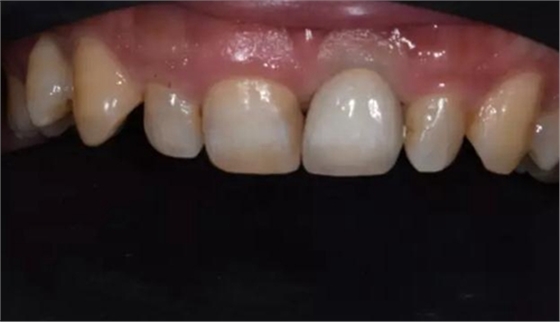

病例1:C先生,36歲,門牙外傷后拔除后3月。就診要求修復(fù)。

缺牙區(qū)比色照

評估C先生身體狀況和口腔內(nèi)情況后。選擇了種植修復(fù)。

修復(fù)體試戴,修復(fù)體和原牙顏色上有輕微差異,不過患者本人非常滿意。

修復(fù)后正面口內(nèi)微笑照。